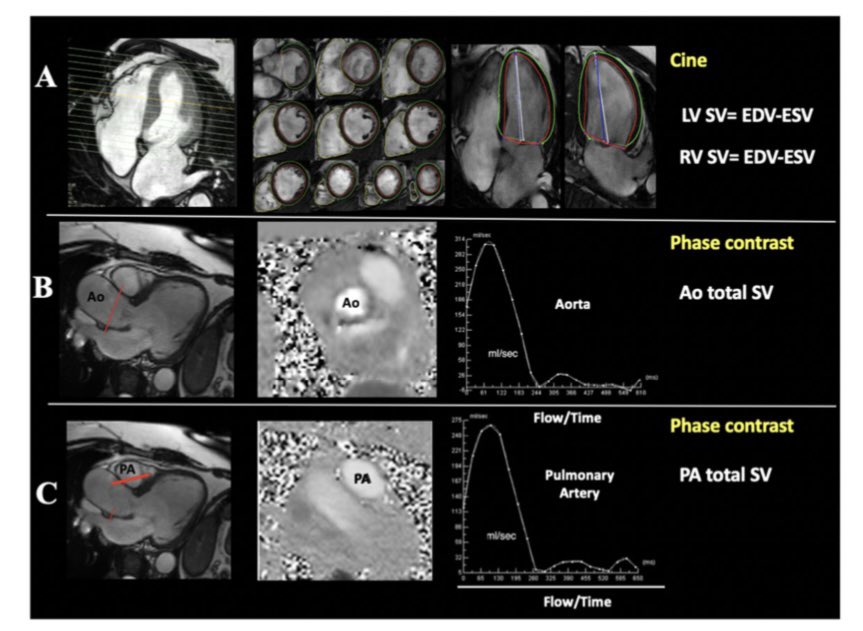

Excited for a state-of-the-art talk by @AmitRPatelMD on the pivotal role of #MultimodalityImaging in heart failure! Don’t miss this deep dive into how #whyCMR and other imaging modalities are transforming diagnosis & management of HF. #SCMR2025